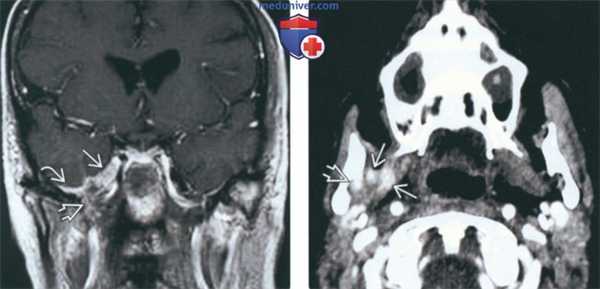

(Слева) Схема коронарной проекции, показана типичная злокачественная опухоль жевательного пространства, которая по волокнам нижнечелюстного нерва распространяется до овального отверстия и полости черепа.

(Справа) Пациент, у которого в анамнезе имеются сведения о пролеченном аде-нокисгозном раке щечного пространства. Онемение в области подбородка заставляет заподозрить рецидив опухоли и наличие периневральной инвазии. При МРТ Т1ВИ с КУ в коронарной проекции определяется опухоль, поражающая нижнечелюстной нерв в области жевательного пространства носоглотки. Опухоль проходит через овальное отверстие Я и начинает прорастать в тройничную полость. (Слева) МРТ Т1ВИ FS с КУ, аксиальная проекция, этот же пациент. Периневральное распространение опухоли в области нижнечелюстного отверстия. Обратите внимание, что с противоположной стороны накопление контраста минимальное. Однозначно, если рентгенолог целенаправленно не обращает внимание на этот признак, поставить правильный диагноз будет невозможно.

(Справа) МРТ Т1ВИ FS с КУ, аксиальная проекция, этот же пациент. Вокруг нижнечелюстного нерва, идущего в сторону овального отверстия, визуализируется опухолевая ткань, накапливающая контрастное вещество.